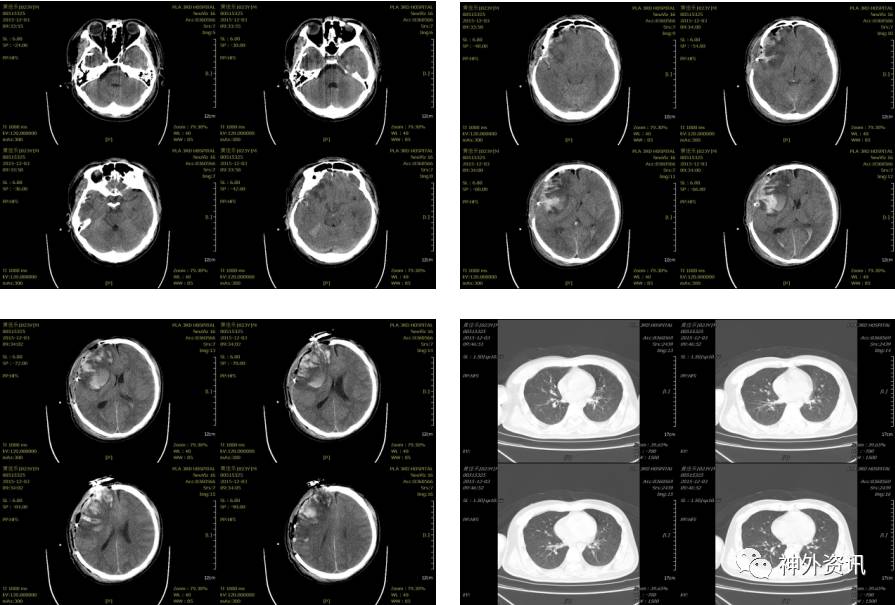

入科后急诊在全麻下行去骨瓣减压及硬膜下血肿清除术,植入脑实质内颅内压监测,术后患者颅内压正常范围,生命体征平稳,术后第二日复查头颅CT及胸部CT(术后约14小时,2015-12-03 09:33):

患者术后虽然颅内显示正常,但挫伤出血量大,脑肿胀明显,行二次开颅颅内血肿清除术,术后复查头颅示(2015-12-04 09:05):

术后给予镇痛、镇静、机械通气、脱水、止血、抗感染、目标性体温控制、营养支持等治疗,术后4天复查头颅CT及胸部CT示(2016-12-08 10:39):